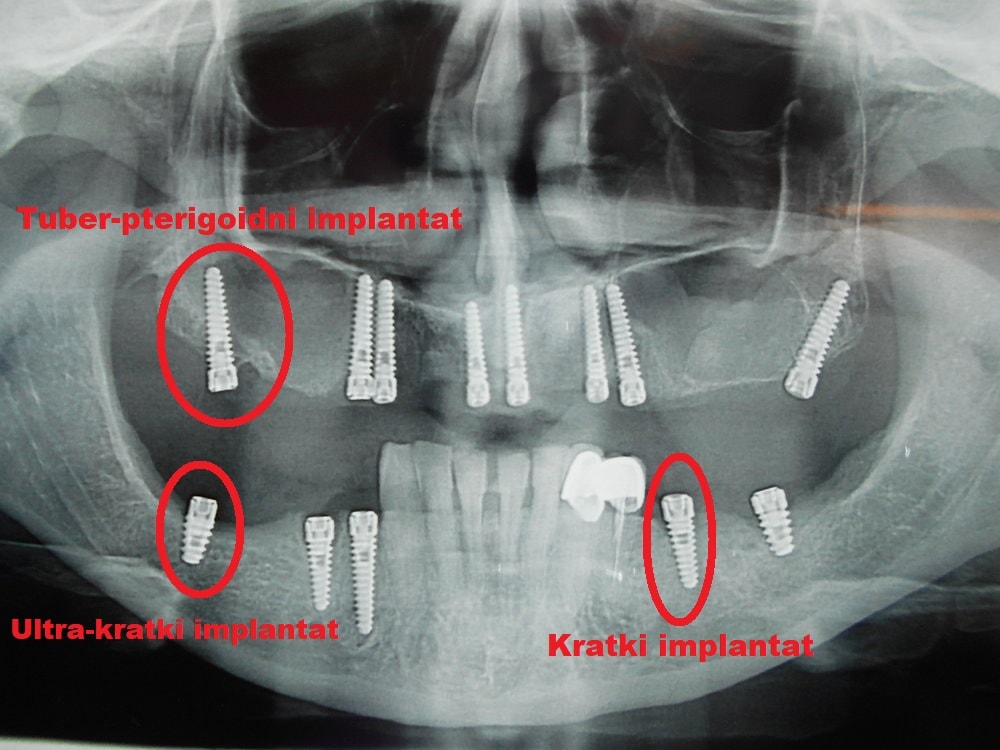

Dentalna implantologija obuhvata hirurške procedure koje imaju za cilj funkcionalnu rehabilitaciju pacijenata upotrebom dentalnih implantata, odnosno metalnih elemenata koji se hirurški ugrađuju u gornju i donju vilicu.

Implantati mogu da imaju različiti oblik, mogu da se ugrade u različitim pozicijama i različitim tehnikama. Trenutno se većina implantata izrađuje od titanijuma.